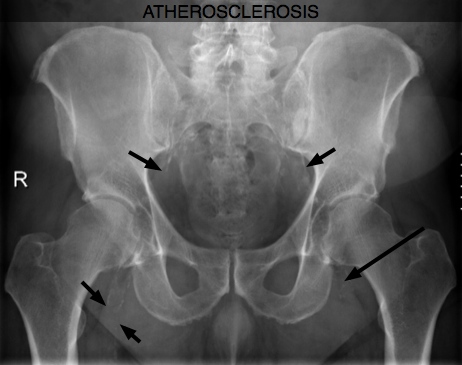

Both chiropractors and surgeons have long suspected that smoking is the greatest risk factor in the treatment of low back pain. New Finnish research now confirms those suspicions ... Atherosclerosis Symptoms and Low Back Pain ...